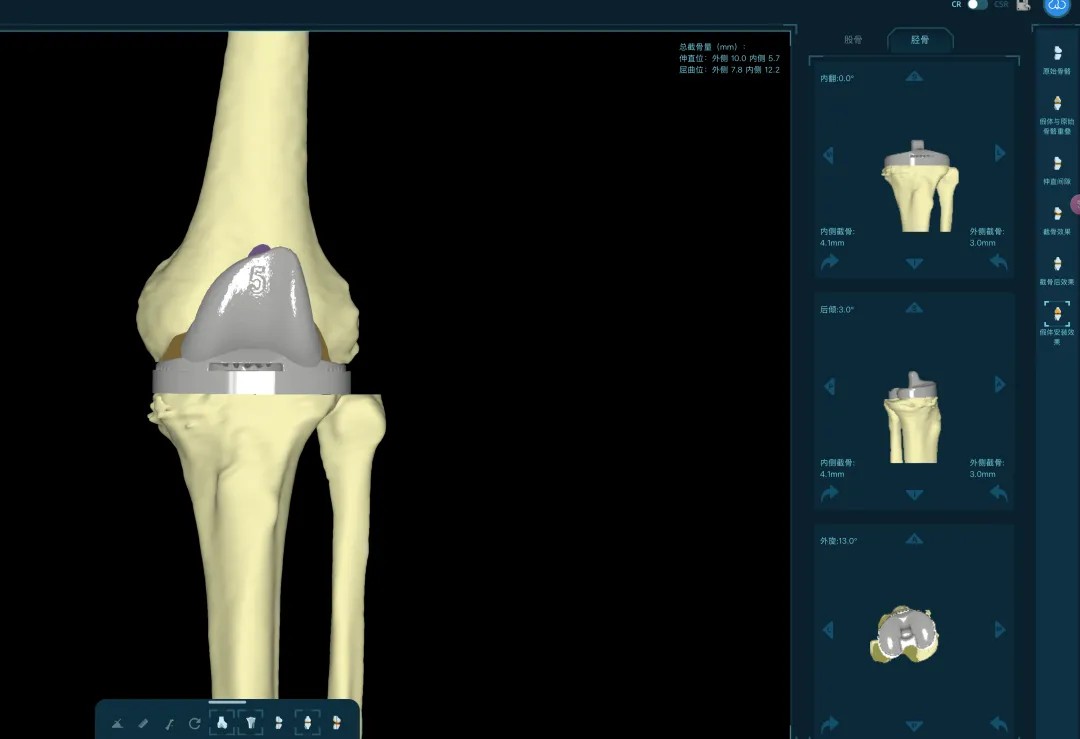

清創(chuàng)只是第一步,如何在一片“復(fù)雜地形”中重建一個穩(wěn)定、功能良好的膝關(guān)節(jié),是更大的挑戰(zhàn)。為此,團隊引入了計算機輔助手術(shù)規(guī)劃系統(tǒng)。

通過患者的CT數(shù)據(jù),系統(tǒng)構(gòu)建出膝關(guān)節(jié)的三維數(shù)字模型,精確評估骨缺損的范圍與形態(tài)。醫(yī)生可以在虛擬空間中,提前模擬手術(shù)過程,為患者“量體裁衣”,規(guī)劃出假體安放的最佳位置、角度以及所需填充骨缺損的特殊墊塊型號。

“這相當于在真實戰(zhàn)斗前,進行了一次全方位的沙盤推演。”羅軍介紹,這種規(guī)劃確保了手術(shù)的精準度,縮短了手術(shù)時間,也為使用先進的翻修假體系統(tǒng)做好了完美鋪墊。

本次手術(shù)的核心,是采用了Evolution® ECCK膝關(guān)節(jié)翻修系統(tǒng)。該系統(tǒng)專為應(yīng)對翻修手術(shù)中常見的嚴重骨缺損、韌帶功能不全等極端復(fù)雜情況而設(shè)計。

其模塊化的組件提供了前所未有的靈活性,就像一套高精度的“工程套件”,允許醫(yī)生在術(shù)中根據(jù)實際骨缺損情況,自由組合不同尺寸的墊塊、延長桿等部件,實現(xiàn)關(guān)節(jié)線和力學穩(wěn)定性的個體化重建。